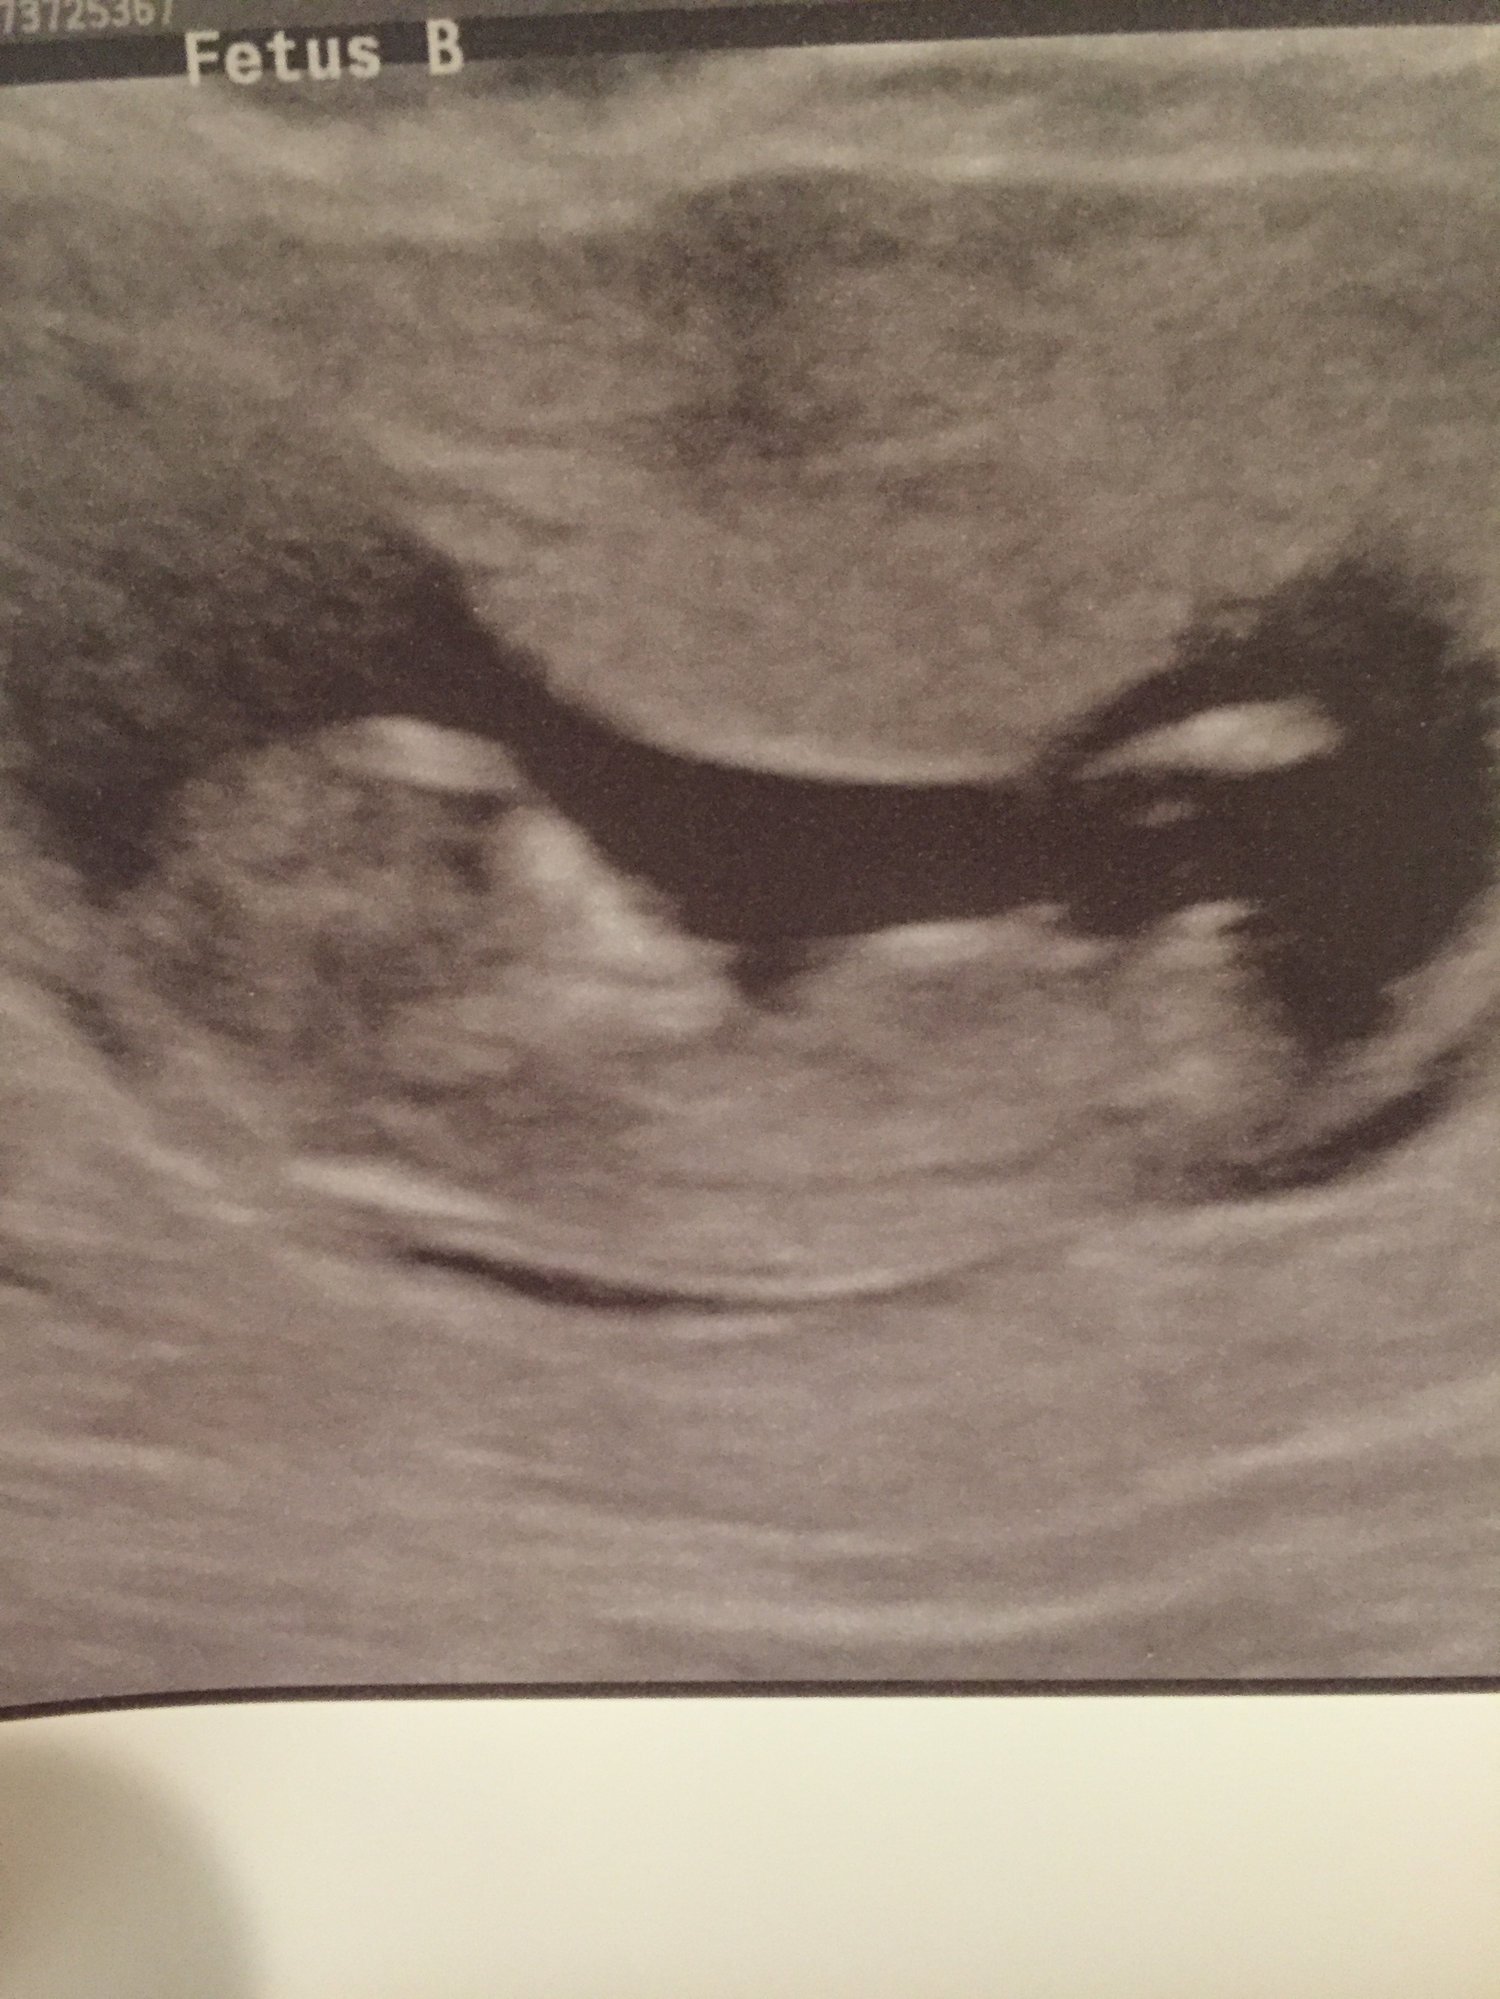

Shots from our NT scan at 12 weeks + 3 days. Measuring right on track, and the tech thought Baby B looked like a boy!

My ultrasound at 13 weeks when I went in for the NT scan! Had no idea that there are two in there !